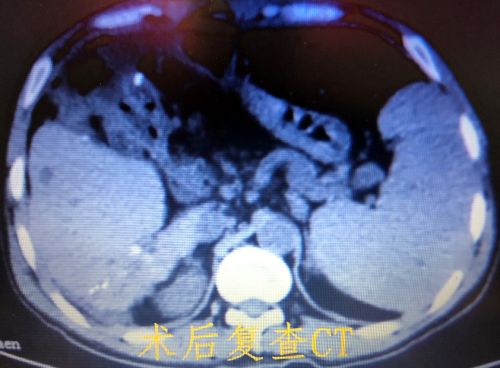

术后复查ct显示结石全都被清除。